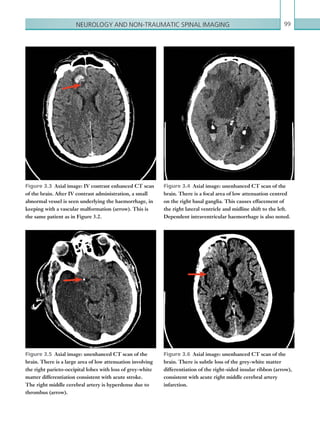

• 61.

Gastrointestinal and genitourinaryimaging 39 Figure 2.20  Axial image: IV contrast enhanced CT scan of the abdomen in the portal venous phase. There is a wedge-shaped low attenuation within the spleen in keeping with an infarct. Figure 2.21  Axial image: IV contrast enhanced CT scan of the abdomen in the portal venous phase. ­Multiple locules of gas can be seen within the wall of the bowel, secondary to bowel ischaemia. Figure 2.22  Axial images: IV contrast enhanced CT scan of the abdomen in the portal venous phase. Large volumes of portal venous gas are seen within the liver extending to the periphery. Figure 2.23  Axial image: IV contrast enhanced CT scan of the abdomen in the portal venous phase. The mesenteric vessels are engorged and the mesenteric fat has a hazy appearance. K22247_C002.indd 39 16/05/15 3:07 AM

• 62.

Chapter 240 backwash ileitis).Infective enterocolitis can affect any part of the bowel (Table 2.7). Pseudomembranous colitis commonly affects the descending and transverse colon and typically causes much more pronounced wall thickening (10–15 mm) than other causes (Figure 2.24). Neutropaenic enterocolitis typically involves the terminal ileum, caecum and ascending colon, although ahistoryofchemotherapyandneutropaeniaisthemost helpful tool to make this diagnosis. Utilisation of lung and bone window settings is also useful to identify free intra-abdominal gas, suggestive of associated bowel perforation. Toxic megacolon is a complication of most colitides and is a risk factor for imminent perforation. This is diagnosed when there is colonic dilatation (transverse colon 6 cm) in the presence of associated colonic inflammation. Any suspicion of toxic megacolon should be urgently discussed with the referring team. Plain films The hallmark of enterocolitis on plain radiographs is bowel wall thickening, although again this is a difficult diagnosis to make due to variable bowel collapse (Figure 2.25). A ‘thumbprinting’ pattern can be observed in the colon, representing thickened haustral folds, although this has a wide differential. CAUSATIVE ORGANISM DISTRIBUTION Clostridium difficile (pseudomembranous colitis) Descending and transverse colon. Salmonella spp. Colonic inflammation only. Campylobacter spp. Typically in distal colon. Yersinia spp. Typically terminal ileum and caecum. Mycobacterium spp. Typically terminal ileum and caecum. Entamoeba histolytica Diffuse colonic involvement, typically ascending colon. Shigella spp. Typically rectosigmoid colon. Table 2.7 Typical distribution of infective colitides. Figure 2.24  Axial image: IV contrast enhanced CT scan of the abdomen in the portal venous phase. There is marked bowel wall thickening ­involving the ­descending colon (arrow), typically seen in ­pseudomembranous colitis. Figure 2.25  Supine abdominal radiograph. There is thickening of the bowel wall involving the descending colon (arrow), consistent with colitis. No intraperitoneal free gas is seen. K22247_C002.indd 40 16/05/15 3:07 AM

• 63.

Gastrointestinal and genitourinaryimaging 41 LARGE BOWEL OBSTRUCTION Large bowel obstruction (LBO) is a common surgical emergency that can occur as a result of many varying pathologies. One of the commonest causes of LBO in western countries is malignancy, usually as a result of primary large bowel carcinoma (Khurana et al., 2002). Invasive malignancies may infiltrate the mucosa, eventually occluding the lumen and resulting in obstruction. Chronic diverticulitis and radiotherapy to the pelvis may lead to fibrosis and stricturing of the bowel. Large bowel volvulus is another common cause of obstruction; this occurs when there is twisting of the mesentery resulting in a closed loop obstruction. This leads to bowel obstruction; however, the closed loop of bowel is also at risk of ischaemia. Causes of LBO include: • Colonic malignancy. • Inflammatory strictures: Crohn’s, ischaemia, diverticulitis. • Volvulus. • Infective processes: TB, amoebiasis. • Extrinsic lesions: abscess, bladder/prostate/uterine tumour, endometriosis. Clinically, patients may present with abdominal pain, distension and vomiting. They may also report an inability to pass stool or flatus. If complicated by perforation, patients may demonstrate peritonism and haemodynamic instability (see Bowel perforation). Urgent imaging is often necessary to help plan surgery.ThemanagementofLBOvariesdependingon the underlying aetiology. Most cases typically require surgical resection for relief of symptoms, although lesions that cannot be completely resected may instead undergo bowel defunctioning and creation of a stoma. In palliative cases, colonic stents may be inserted in Key points • Enterocolitis may be ischaemic, inflammatory or infective in nature. • Acute bowel ischaemia is a surgical emergency and has a high mortality rate. Prompt diagnosis is essential in order to facilitate urgent surgical treatment. • CT is the modality of choice to investigate cases of bowel ischaemia; however, imaging should not delay emergency laparotomy in strongly suspected cases. • There is significant overlap in the radiological findings of enterocolitis; however, absent or diminished bowel wall enhancement corresponding to an arterial territory is highly suggestive of ischaemia. Report checklist • Presence or absence of free gas, indicative of perforation. • Presence or absence of gas within the bowel wall or the portal venous system. • Presence or absence of filling defects in the coeliac axis/SMA/IMA/SMV or any of their branches. • Consider embolic disease in cases of visceral infarcts. The presence or absence of potential embolic sources (e.g. thrombus in the left atrial appendage/left ventricular aneurysm/infarct/aortic dissection/aortic aneurysm). • Consider a differential diagnosis of additional causes of enterocolitis. Reference Sung ER, Hyun KH, Soo-Hyun L et al. (2000) CT and MR imaging findings of bowel ischemia from various primary causes. RadioGraphics 20:29–42. K22247_C002.indd 41 16/05/15 3:07 AM

• 64.

Chapter 242 Radiological findings Plainfilms On an abdominal plain film, the diagnosis of LBO is made by identifying dilated large bowel loops. In a normal patient, the caecum should not measure more than 8–9 cm and the remainder of the large bowel should not measure more than 5 cm, therefore a bowel diameter greater than these values may suggest underlying LBO (Figure 2.26). The distribution of bowel dilatation is key; in LBO, large bowel collapse distal to the point of obstruction would be expected. Dilated loops of small bowel may also be present, indicating ileocaecal valve incompetence. In cases where a nasogastric (NG) tube has been placed, the tip should be located under the left hemidiaphragm. order to relieve symptoms. Sigmoid volvulus is initially managed conservatively with a rectal flatus tube insertion, but persisting volvuli may require surgical decompression. Radiological investigations An abdominal and erect chest plain film is indicated in patients who present with signs of LBO. An abdominal plain film may confirm the presence of obstruction; however, the underlying cause is unlikely to be apparent. Definitive diagnosis is routinely made with contrast enhanced CT imaging. It is not usually necessary to administer oral contrast, as the level of obstruction is usually identifiable as an abrupt calibre change or mass. Furthermore, patients who are acutely obstructed are unlikely to be able to ingest the volume of oral contrast required to adequately opacify the bowel. It is important to note that large bowel volvulae normally have a typical appearance on plain films and, as a result, CT imaging is not routinely required to make this diagnosis. The use of water soluble single contrast enema has largely been replaced with CT, though some centres may still practise this. Contrast administered rectally flows proximally through the large bowel and does not pass beyond the point of obstruction. If the procedure is performed, water soluble contrast should be used due to the risk of bowel perforation and hence leakage into the peritoneum. (See Table 2.8.) MODALITY PROTOCOL CT IV contrast, portal venous phase: 100 ml IV contrast, 4 ml/sec via 18G cannula. Scan at 70 seconds. Scan from just above the ­diaphragm to just below the pubic symphysis. Plain film imaging Erect CXR to include the diaphragm. ­Abdominal plain film imaging to include the liver to the pubic symphysis. Table 2.8 Large bowel obstruction. Imaging protocol. Figure 2.26  AP radiograph of the abdomen. Dilated loops of large bowel are seen in the right abdomen, ­indicated by the lack of valvulae conniventes. The ­ileocaecal valve is patent, resulting in reflux of gas into small bowel loops seen centrally and in the left abdomen. K22247_C002.indd 42 16/05/15 3:07 AM

• 65.

Gastrointestinal and genitourinaryimaging 43 LBO secondary to malignancy or stricture formation may have similar radiological findings; however, volvulae tend to have a slightly different appearance, which can often allow them to be diagnosed on plain film images. Sigmoid volvulus is the commonest type of volvulus, and occurs when the colon twists about its mesentery. It tends to occur in slightly older patients compared with those who have a caecal volvulus. The classic findings include the presence of a ‘coffee bean’ appearance to the dilated loop, an inverted ‘U’ shape and the loop extending into the upper abdomen from the pelvis (Figure 2.27). The sigmoid colon is also usually ahaustral in comparison with caecal volvulus, which normally retains its normal haustral pattern. The other main feature of caecal volvulus is extension of the dilated loop of bowel from the right lower quadrant to the left upper quadrant. The differences between sigmoid and caecal volvulae are summarised in Table 2.9. SIGMOID CAECAL Typical plain film findings Coffee bean sign. Large bowel dilatation proximally. Ahaustral closed loop. Inferior convergence in the LIF. Left flank overlap sign. Dilated caecum may be seen in the mid abdo- men or LUQ. Haustrations usually present. Associated small bowel dilatation. LIF = left iliac fossa; LUQ = left upper quadrant. Table 2.9  Sigmoid vs. caecal volvulus. Computed tomography IV contrast enhanced CT is used not only to diagnose the presence of LBO, but also the underlying cause, allowing evaluation of luminal and extraluminal bowel structures. Initial review of the CT should begin by confirming the presence of LBO, indicated by large bowel dilatation proximal to an abrupt transition point. The same numerical values should be used as for plain film imaging (see above). Dilated large bowel loops should be traced distally in order to identify a mechanical cause of the obstruction. This can usually be seen as a transition in the calibre of the bowel from dilated to normal, or often collapsed beyond the point of obstruction. A quick review on lung window settings (width 1,500, level 500) is helpful to reveal any evidence of free intra-abdominal gas, suggestive of bowel perforation. If this is seen, the surgical team should be informed as a matter of urgency as the patient may require emergency surgery. Figure 2.27  AP radiograph of the abdomen. There are dilated loops of large bowel, which arise from the pelvis with an inverted ‘U’ appearance suggestive of sigmoid volvulus. K22247_C002.indd 43 16/05/15 3:07 AM

• 66.

Chapter 244 Large bowelvolvulus has a distinctive appearance on CT imaging. Proximal loops of dilated large bowel are visible, as seen with other causes of obstruction; however, the transition point is seen as a tapering of the bowel lumen to a point of completely collapsed bowel. It is vitally important to scrutinise the extraluminal appearance in these cases. The underlying cause of volvulus (both caecal and sigmoid) is a twisting of the mesentery. On CT, this can be seen as a ‘swirling’ of vessels that appear to rotate about the axis of torsion (Figure 2.30) at the site of the involved loop of bowel. The axis of twisting may not be easily seen on axial imaging, and coronal and sagittal reformats should therefore be used to confirm the diagnosis. Incaseswherethereislargeboweldilatationwithout a mechanical cause of obstruction, colonic pseudo- obstruction may be present. Pseudo-obstruction is diagnosed when there are symptoms of bowel obstruction and there is large bowel dilatation on imaging, but no identifiable mechanical obstruction. Often there is a gradual tapering of the bowel rather than an immediate point of transition. Alternatively, In cases of malignant obstruction, a soft tissue mass can often be seen occluding the lumen (Figure 2.28). Subtle tumours can be easy to miss, manifesting as concentric or eccentric mural thickening. Advanced tumours may also demonstrate extension through the serosa, adjacent lymphadenopathy or distant metastases (usually to the liver, appearing as ill-defined flow attenuation lesions). Obstruction secondary to stricture formation may be seen as a narrowed segment of bowel at the point of calibre transition (Figure 2.29). This can be a difficult diagnosis to make on a single study since physiologically collapsed bowel can have a similar appearance; correlation with previous imaging is useful in this regard. In general, malignancies tend to be shorter segment areas of mural thickening, whereas strictures tend to be longer segments of collapsed bowel; however, it can often be difficult to exclude the presence of a small malignant obstructing lesion within a stricture (particularly in the absence of adequate bowel preparation). Colonoscopy is therefore often needed and should be recommended in order to assess the abnormal segments of bowel in further detail. Figure 2.28  Axial image: IV contrast enhanced CT scan of the abdomen and pelvis in the portal venous phase. A solid mass lesion is seen within the mid-­ sigmoid colon (arrow), occluding the lumen and ­resulting in upstream dilatation of the bowel. Figure 2.29  Axial image: IV contrast enhanced CT scan of the abdomen in the portal venous phase. There is a long stricture of the mid-sigmoid colon with a ­massively dilated loop of proximal sigmoid colon shown. A single diverticulum is shown in this image. The ­stricture was due to chronic diverticulitis. K22247_C002.indd 44 16/05/15 3:07 AM

• 67.

Gastrointestinal and genitourinaryimaging 45 Report checklist • Degree and level of bowel obstruction. • Presence or absence of complications such as perforation or bowel ischaemia. • Consider underlying causes such as malignancy or post-inflammatory strictures. • Document the degree of local or distant disease in cases of malignancy; this determines whether the patient has palliative as opposed to curative surgical treatment. References Choi JS, Lim JS, Kim H et al. (2008) Colonic pseudoobstruction: CT findings. Am J Roentgenol 190:1521–1526. KhuranaB,LedbetterS,McTavishJ et al.(2002)Bowel obstruction revealed by multidetector CT. Am J Roentgenol 178:1139–1144. multiple segments of colonic dilatation and collapse are seen, the distribution of which is not suggestive of mechanical obstruction. Patients with pseudo- obstruction tend to suffer with constipation, with a suggested underlying cause thought to be related to the intrinsic nerve supply of the bowel (Choi et al., 2008). Key points • Large bowel obstruction is a surgical emergency which, if left untreated, may result in bowel perforation or ischaemia. • CT imaging can confirm the diagnosis and identify the underlying cause, although the presence of LBO may be confirmed on plain film images. • LBO is suggested on CT imaging by large bowel dilatation (caecum 8–9 cm, remainder of large bowel 5 cm) proximal to a focal transition point, usually with large bowel collapse distally. Figure 2.30  Coronal image: IV contrast enhanced CT scan of the abdomen and pelvis in the portal venous phase. A loop of sigmoid colon can be seen in the midline, which comes to an abrupt stop (arrow). The adjacent vessels demonstrate a swirling appearance, ­suggestive of twisting of the mesentery. K22247_C002.indd 45 16/05/15 3:07 AM

• 68.

Chapter 246 GALLSTONE ILEUS Gallstoneileus is an uncommon cause of mechanical small bowel obstruction (SBO). It is a complication of chroniccholecystitisandoccurswhenagallstonepasses through a cholecystenteric fistula located between the gallbladder and the duodenum. The gallstone impacts within the small bowel, resulting in SBO. Overall, gallstone ileus is an uncommon cause of SBO (4%), but in the elderly population it is more common, accounting for up to 25% of non- strangulated bowel obstructions and resulting in significant morbidity in this group (Lassandro et al., 2005). Pathologically, gallstone ileus results from repeated boutsofcholecystitisresultinginadhesionsbetweenthe gallbladder and the small bowel (usually duodenum), eventually leading to fistula formation and passage of gallstones into the lumen of the bowel. Patients usually present with a long history of recurrent right upper quadrant pain, in keeping with chronic cholecystitis. The acute presentation of gallstone ileus is that of a small bowel obstruction, with colicky abdominal pain and abdominal distension. Radiological investigations A plain abdominal radiograph is useful as a first-line investigationinpatientswithsuspectedSBO.Suspicion of gallstone ileus on plain film imaging necessitates CT imaging of the abdomen, which has a sensitivity, specificity and accuracy of diagnosing gallstone ileus of 93%, 100% and 99%, respectively (Yu et al., 2005). Ultrasound is useful in assessment of patients with right upper quadrant pain to identify the presence of gallstones or cholecystitis. (See Table 2.10.) Radiological findings Plain films The classic findings on an abdominal radiograph are of SBO (dilated loops of small bowel 2.5 cm), gas within the biliary tree (linear branching lucencies projected over the right upper quadrant) and a gallstone (usually in the right iliac fossa) (Figure 2.31). This is known as Rigler’s triad. MODALITY PROTOCOL CT IV contrast, portal venous phase: 100 ml IV contrast, 4 ml/sec via 18G cannula. Scan at 70 seconds. Scan from just above the diaphragm to just below the pubic symphysis. Plain film imaging Abdominal plain film imaging to ­include the liver to the pubic ­symphysis. Ultrasound 1–5MHz curvilinear probe. Table 2.10  Galltone ileus. Imaging protocol. Figure 2.31  AP abdominal radiograph. Multiple loops of dilated small bowel can be seen, consistent with SBO. Linear, branching lucencies can be seen at the right upper quadrant consistent with biliary gas (arrow). The ­findings are consistent with gallstone ileus. No ­radiopaque ­gallstone can be seen on the radiograph. K22247_C002.indd 46 16/05/15 3:07 AM

• 69.

Gastrointestinal and genitourinaryimaging 47 Computed tomography Appearances on CT are similar to those seen on plain film images. SBO is present with dilated fluid-filled small bowel loops measuring 3.5 cm. As with any case of obstruction, the entire length of bowel must be traced. A transition point (abrupt calibre change between dilated and non-dilated bowel) may be identified and is the likely site of the impacted gallstone (Figure 2.32). Care should be taken, as not all gallstones are calcified (12%) and they may be of similar density to the bowel contents (Lassandro et al., 2005). Multiple stones may also be present. Pneumobilia on CT is identified as branching air- filled structures in the liver (Figure 2.33). These can be differentiated from similar appearances of portal venous gas, as air in the biliary tree does not extend to the periphery of the liver, unlike portal venous gas. Causes of pneumobilia are listed in Table 2.11. Figure 2.33  Axial image: IV contrast enhanced CT scan of the abdomen in the portal venous phase. Gas is seen within the biliary tree (arrow). There is a small volume of fluid around the liver. • Recent endoscopic retrograde cholangiopancreatography or percutaneous transhepatic cholangiography. • Gallstone ileus. • Biliary enteric anastomosis (e.g. Whipple’s). • Peptic ulcer disease. • Traumatic. • Emphysematous cholecystitis. • Incompetent sphincter of Oddi (sphicterotomy, chronic pancreatitis and passage of stone). • Congenital. Table 2.11  Causes of ­pneumobilia. Figure 2.32  Axial image: IV contrast enhanced CT scan of the abdomen and pelvis in the portal venous phase. A rounded, hyperdense gallstone is seen within the lumen of a small bowel loop in the right iliac fossa. Loops of fluid-filled, dilated small bowel can also be seen. K22247_C002.indd 47 16/05/15 3:07 AM

• 70.

Chapter 248 • Afistulous tract may be seen between the gallbladder and the duodenum and this may be associated with surrounding inflammation and locules of free gas. • It is important to distinguish between portal venous gas and biliary air, which appear similar on CT, the latter not extending to the periphery of the liver. Report checklist • Degree of bowel obstruction/dilatation associated with gallstone ileus. • Presence or absence of associated collections in the gallbladder bed. • Presence or absence of overt free intraperitoneal gas. References Lassandro F, Romano S, Ragozzino A et al. (2005) Role of helical CT in diagnosis of gallstone ileus and relatedconditions. Am J Roentgenol 185:1159–1165. Yu CY, Lin CC, Shyu RY et al. (2005) Value of CT in the diagnosis and management of gallstone ileus. World J Gastroenterol 11:2142–2147. Inflammatory changes may be seen around the gallbladder and second part of the duodenum, with thickening of the gallbladder wall, pericholecystic fluid and surrounding inflammatory fat stranding. There mayalsobeloculesoffreegasandevidenceofthefistula between the gallbladder and duodenum. Occasionally, the inflamed gallbladder can adhere to ascending colon and the gallstone can pass into the large bowel. This may then lead to passage of the stone or it can become obstructed, depending on the size of the stone (Figures 2.34, 2.35). If gallstone ileus is present, the surgical team should be informed; treatment options are usually surgically based, although some patients are managed conservatively. Key points • An AXR showing Rigler’s triad is diagnostic for gallstone ileus. • CT features are similar to those seen on plain film images. The entire bowel should be carefully inspected to identify the transition point or gallstone(s). Figure 2.34  Axial image: unenhanced CT scan of the abdomen. There is thickening of the gallbladder wall, consistent with acute cholecystitis. Figure 2.35  Axial image: unenhanced CT scan of the abdomen. There is an impacted gallstone in the sigmoid colon. K22247_C002.indd 48 16/05/15 3:07 AM

• 71.